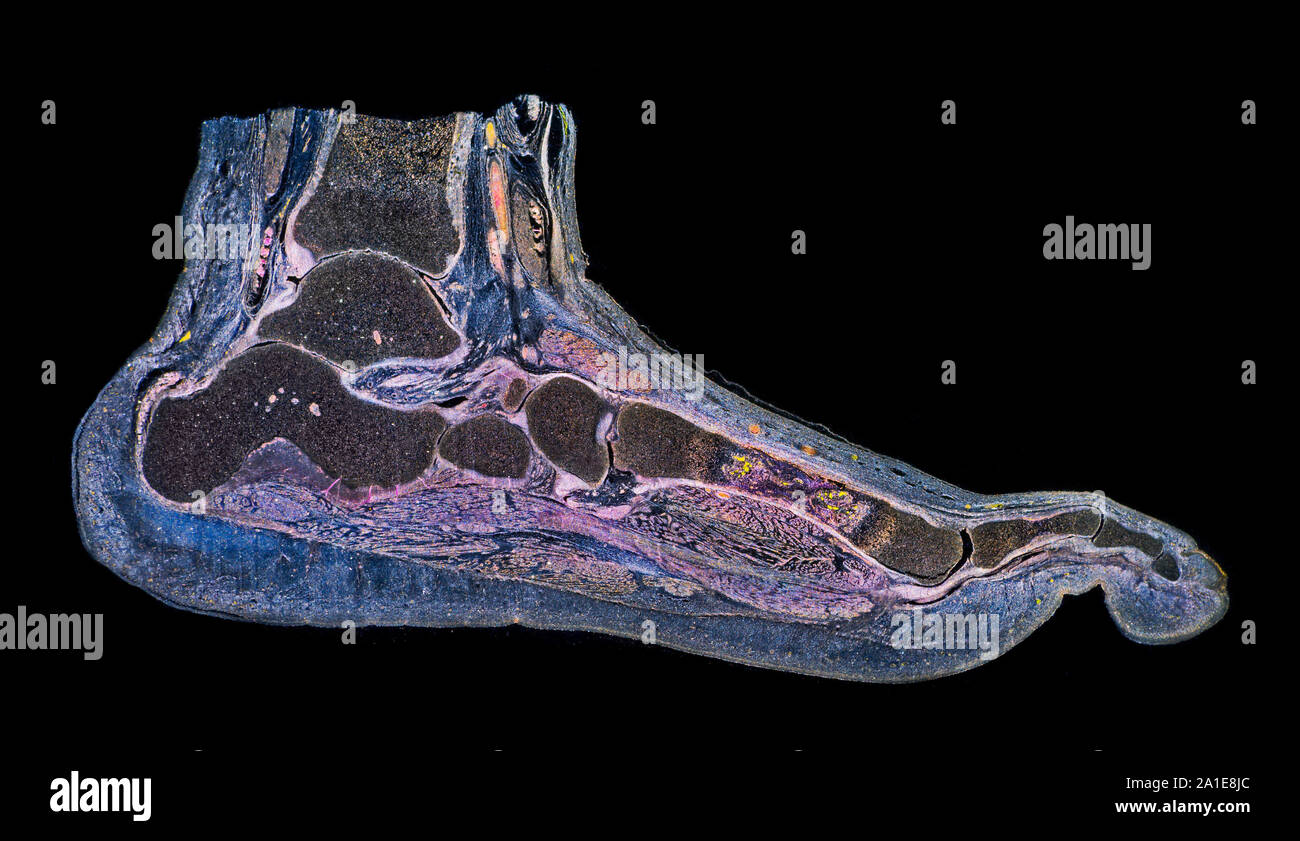

RF2ABM669–La médecine et les soins de l'illustre le tableau, les droits de l'anatomie du pied : Peau et tissus ectodermaux, os, muscles nerfs, vaisseaux sanguins

RF2FX3HF0–Fasciite plantaire. Illustration anatomie du pied humain expliquer sur le symptôme fasciite plantaire.